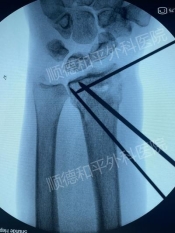

病例1:林女士(化名),74岁,左桡骨远端闭合性骨折+左尺骨茎突骨折

外院手法复位+石膏固定后仍疼痛难忍,家属寻求更优治疗。

治疗方案:关节镜辅助下桡骨远端骨折复位+可吸收螺钉+克氏针内固定术。手术仅1小时,创口微小,术后肿胀轻,疼痛显著减轻。患者快速康复,家属反馈:“终于不用看她天天忍痛了!”